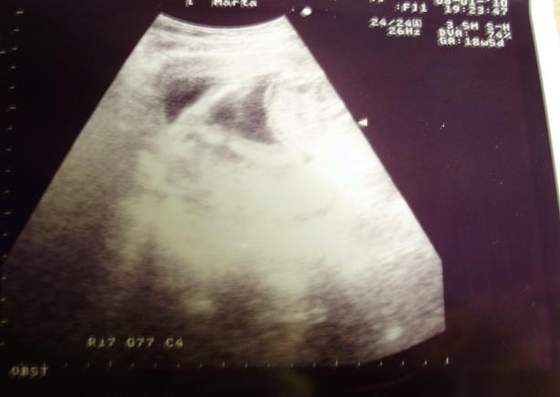

A to świeżutkie zdjęcia mojego "zagadkowego" nadal dzidziusia :-)

na tym pierwszym zdjęciu, myślałam,że to siusiak, ale to jest pępowina :-)![]()